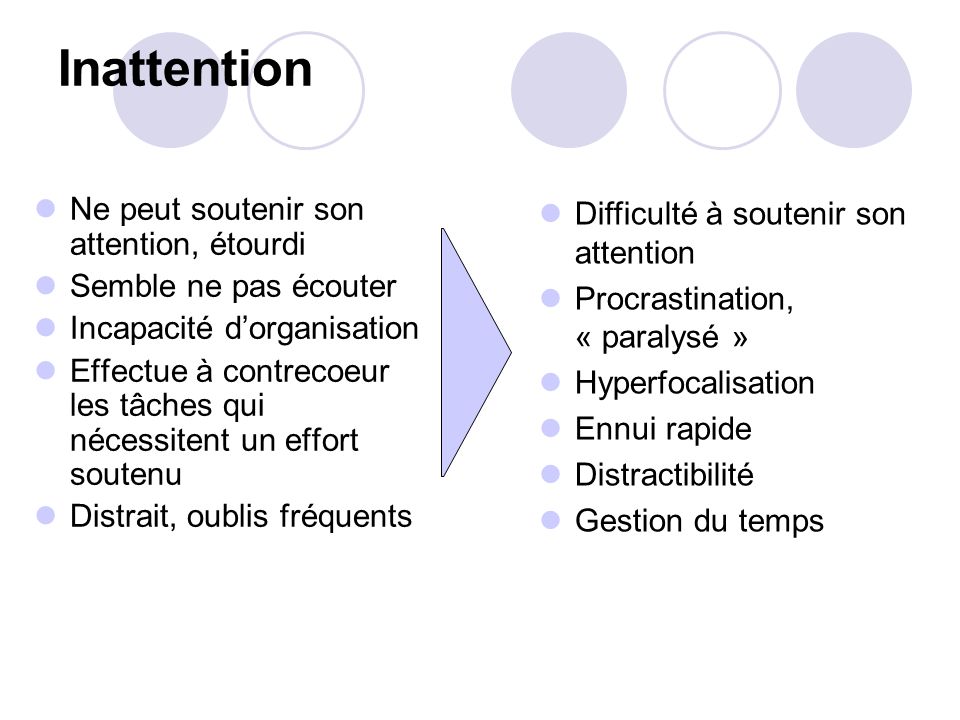

■ Les 3 types élémentaires du TDAH adulte

– Le déficit

d’attention est la base du TDAH et il se décline en 3 types qui se

différencient fortement sur l’aspect comportemental

:

■

Type inattentif

C’est la base de ce trouble et c’est plus une inconsistance de

l’attention qu’un déficit d’attention. Ce

sous-type concerne un peu plus les jeunes filles et les femmes.

– Ceux qui ont uniquement cette

composante sont des rêveurs et passent

d’une idée à l’autre, souvent sans les mettre en action et donc en

commençant peu d’actions.

– Distraits, étourdis, démotivés

chroniques, indécis, capable d’hyperfocaliser aussi, ils ne sont

pas souvent diagnostiqués TDAH, car ils ne dérangent pas leur entourage

et sont à l’opposé de l’hyperactivité au niveau comportemental.

– Ils

sont au contraire hypoactifs et peuvent même sembler apathiques aux yeux

des autres.

■

Type hyperactif

Très médiatisé chez les enfants durant ces dernières années, les adultes

hyperactifs sont devenus avec l’âge moins agité physiquement, mais

passent inlassablement d’une action à

un autre sans en terminer la plupart, les empêchant d’atteindre leurs

objectifs trop nombreux ou incompatibles avec leur trouble.

– Ce sous-type

concerne un peu plus les jeunes garçons et les hommes.

– Ne pas confondre

avec les hyper-actifs (en 2 mots), qui ont une multitude d’activités, mais

qui s’organisent bien et mènent généralement à bout ce qu’ils

entreprennent.

■

Type impulsifTrès médiatisé chez les enfants durant ces dernières années, les adultes hyperactifs sont devenus avec l’âge moins agité physiquement, mais passent inlassablement d’une action à un autre sans en terminer la plupart, les empêchant d’atteindre leurs objectifs trop nombreux ou incompatibles avec leur trouble.

– Ce sous-type concerne un peu plus les jeunes garçons et les hommes.

– Ne pas confondre avec les hyper-actifs (en 2 mots), qui ont une multitude d’activités, mais qui s’organisent bien et mènent généralement à bout ce qu’ils entreprennent.

Ils agissent ou parlent avant de réfléchir, prennent des risques, ont un tempérament explosif ou simplement plaquent tout régulièrement.

– Cela peut être visible de l’extérieur (plus masculin) ou rester interne, et cela peut induire d’étranges comportements irréguliers, avec une vie interne très mouvementée, alternant les émotions agréables et désagréables très rapidement.

– Ils peuvent avoir tendance à interrompre les autres dans une conversation, à consommer des drogues légales et illégales pour calmer cette impulsivité